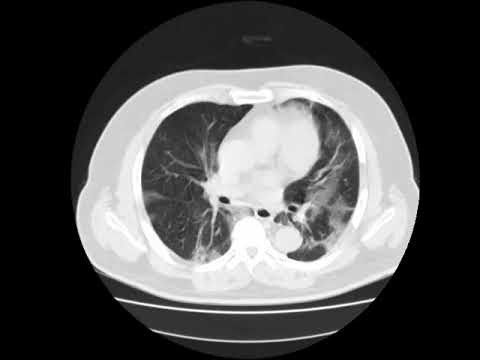

HRCT scans of the chest. A: This image obtained at the ...

HRCT scans of the chest. A: This image obtained at the ... from www.researchgate.net